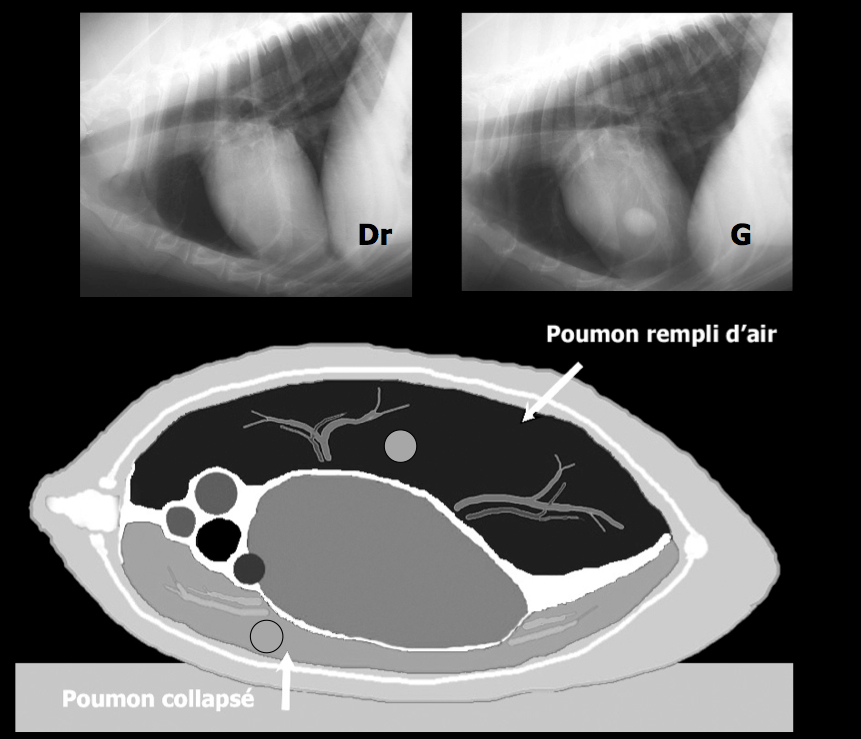

L’emploi de trois vues radiographiques pour la recherche de métastases pulmonaires est devenu une routine en pratique des animaux de compagnie. Mais pourquoi au juste ? Et pourquoi seulement pour la recherche de métastases ? La présence d’air dans les poumons explique pourquoi les structures tissulaires et liquidiennes, comme le coeur, les vaisseaux, la bordure thoracique du diaphragme sont bien visibles, contrairement aux nodules et vaisseaux hépatiques, par exemple. Or, la présence d’air est aussi nécessaire à la détection des lésions pulmonaires, incluant non seulement les nodules et masses pulmonaires, mais également les lésions de bronchopneumonie et l’oedème dans certains cas. En décubitus latéral, les structures médiastinales suivent la gravité et compriment de façon variable le poumon situé vers le bas. Ceci est particulièrement vrai pour le coeur de gros chiens, qui par sa lourdeur peut complètement affaisser le poumon sous-jacent, éliminant par conséquence l’air nécessaire au contraste radiographique. Dans l’exemple ci-haut, la lésion pulmonaire parfaitement visible en latérale gauche (poumon droit hyperinsufflé) disparaît complètement en latérale droite ! Même chose pour le Bouvier bernois vu récemment, atteint d’un sarcome histiocytaire disséminé. Les nodules/masses pulmonaires bien définies (et multilobée pour la plus grosse) présentes en portion caudoventrale du poumon droit (lobe moyen vraisemblablement plus ou moins le lobe crânial droit) sont typiques de cette fâcheuse tumeur maligne. Ces lésions sont normalement accessibles à l’échographie, car généralement accolées à la paroi thoracique. Chez ce chien, les lésions étaient suspectées sur la DV, mais un diagnostic confiant n’était possible qu’avec la 3e vue. Voilà… comme quoi…